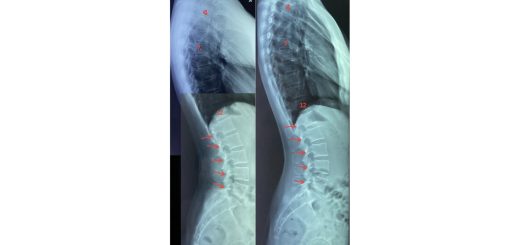

Shortness of Breath due to Hunching (Hyperkyphosis)